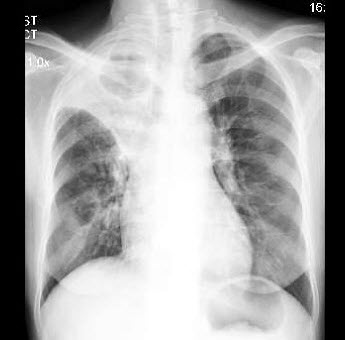

192、多项选择题

男,1岁零8个月,生长发育差,易患呼吸道感染,心悸气促,心脏正、侧位片检查如图所示,正确的描述和诊断是()

A.正位示心影向两侧扩大,心尖左移

B.肺纹理增多

C.侧位示心前间隙变窄,心后食管前三角间隙消失

D.房间隔缺损

E.室间隔缺损